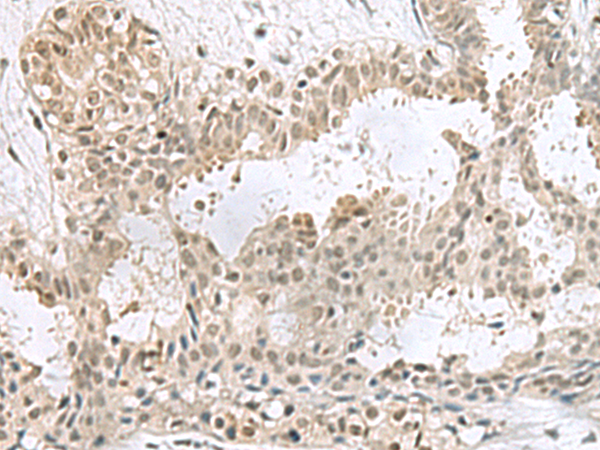

分类: 科研抗体货号: P10207别名: EF1D; EF-1D; FP1047应用: WB,IHC反应种属: Human, Mouse, Rat